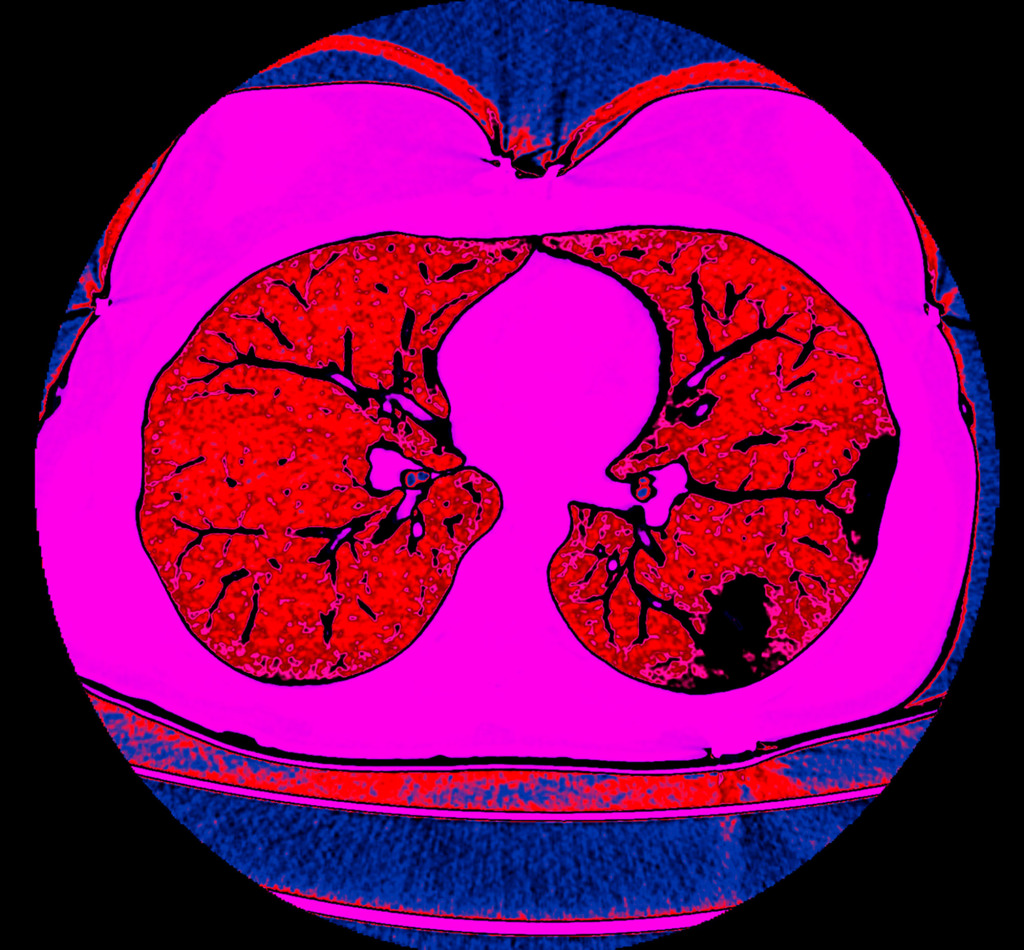

Most of the time, radiologists work with black and white images.

A multi-coloured, bright image is a way to shift the gaze and perceive things differently.

Also, I like to experiment with different photo filters and settings.

The program for processing radiological images (DICOM archives) allows you to create and look at a three-dimensional image from different angles.

If you change the location of the virtual lens, thereby changing the perspective, you can get such images.

No. Tissues with different densities are best suited to visualisation by CT imaging.

Lungs and heart, bones and muscles or organs injected with a contrast agent reveal the best structure and anatomy.